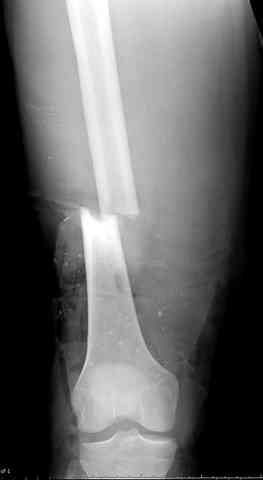

здесь случай с политравмой, перелом зафиксирован наружным фиксатором, после третьей irrigation&debridment фиксация бедра пластиной с последующей кожной пластикой.